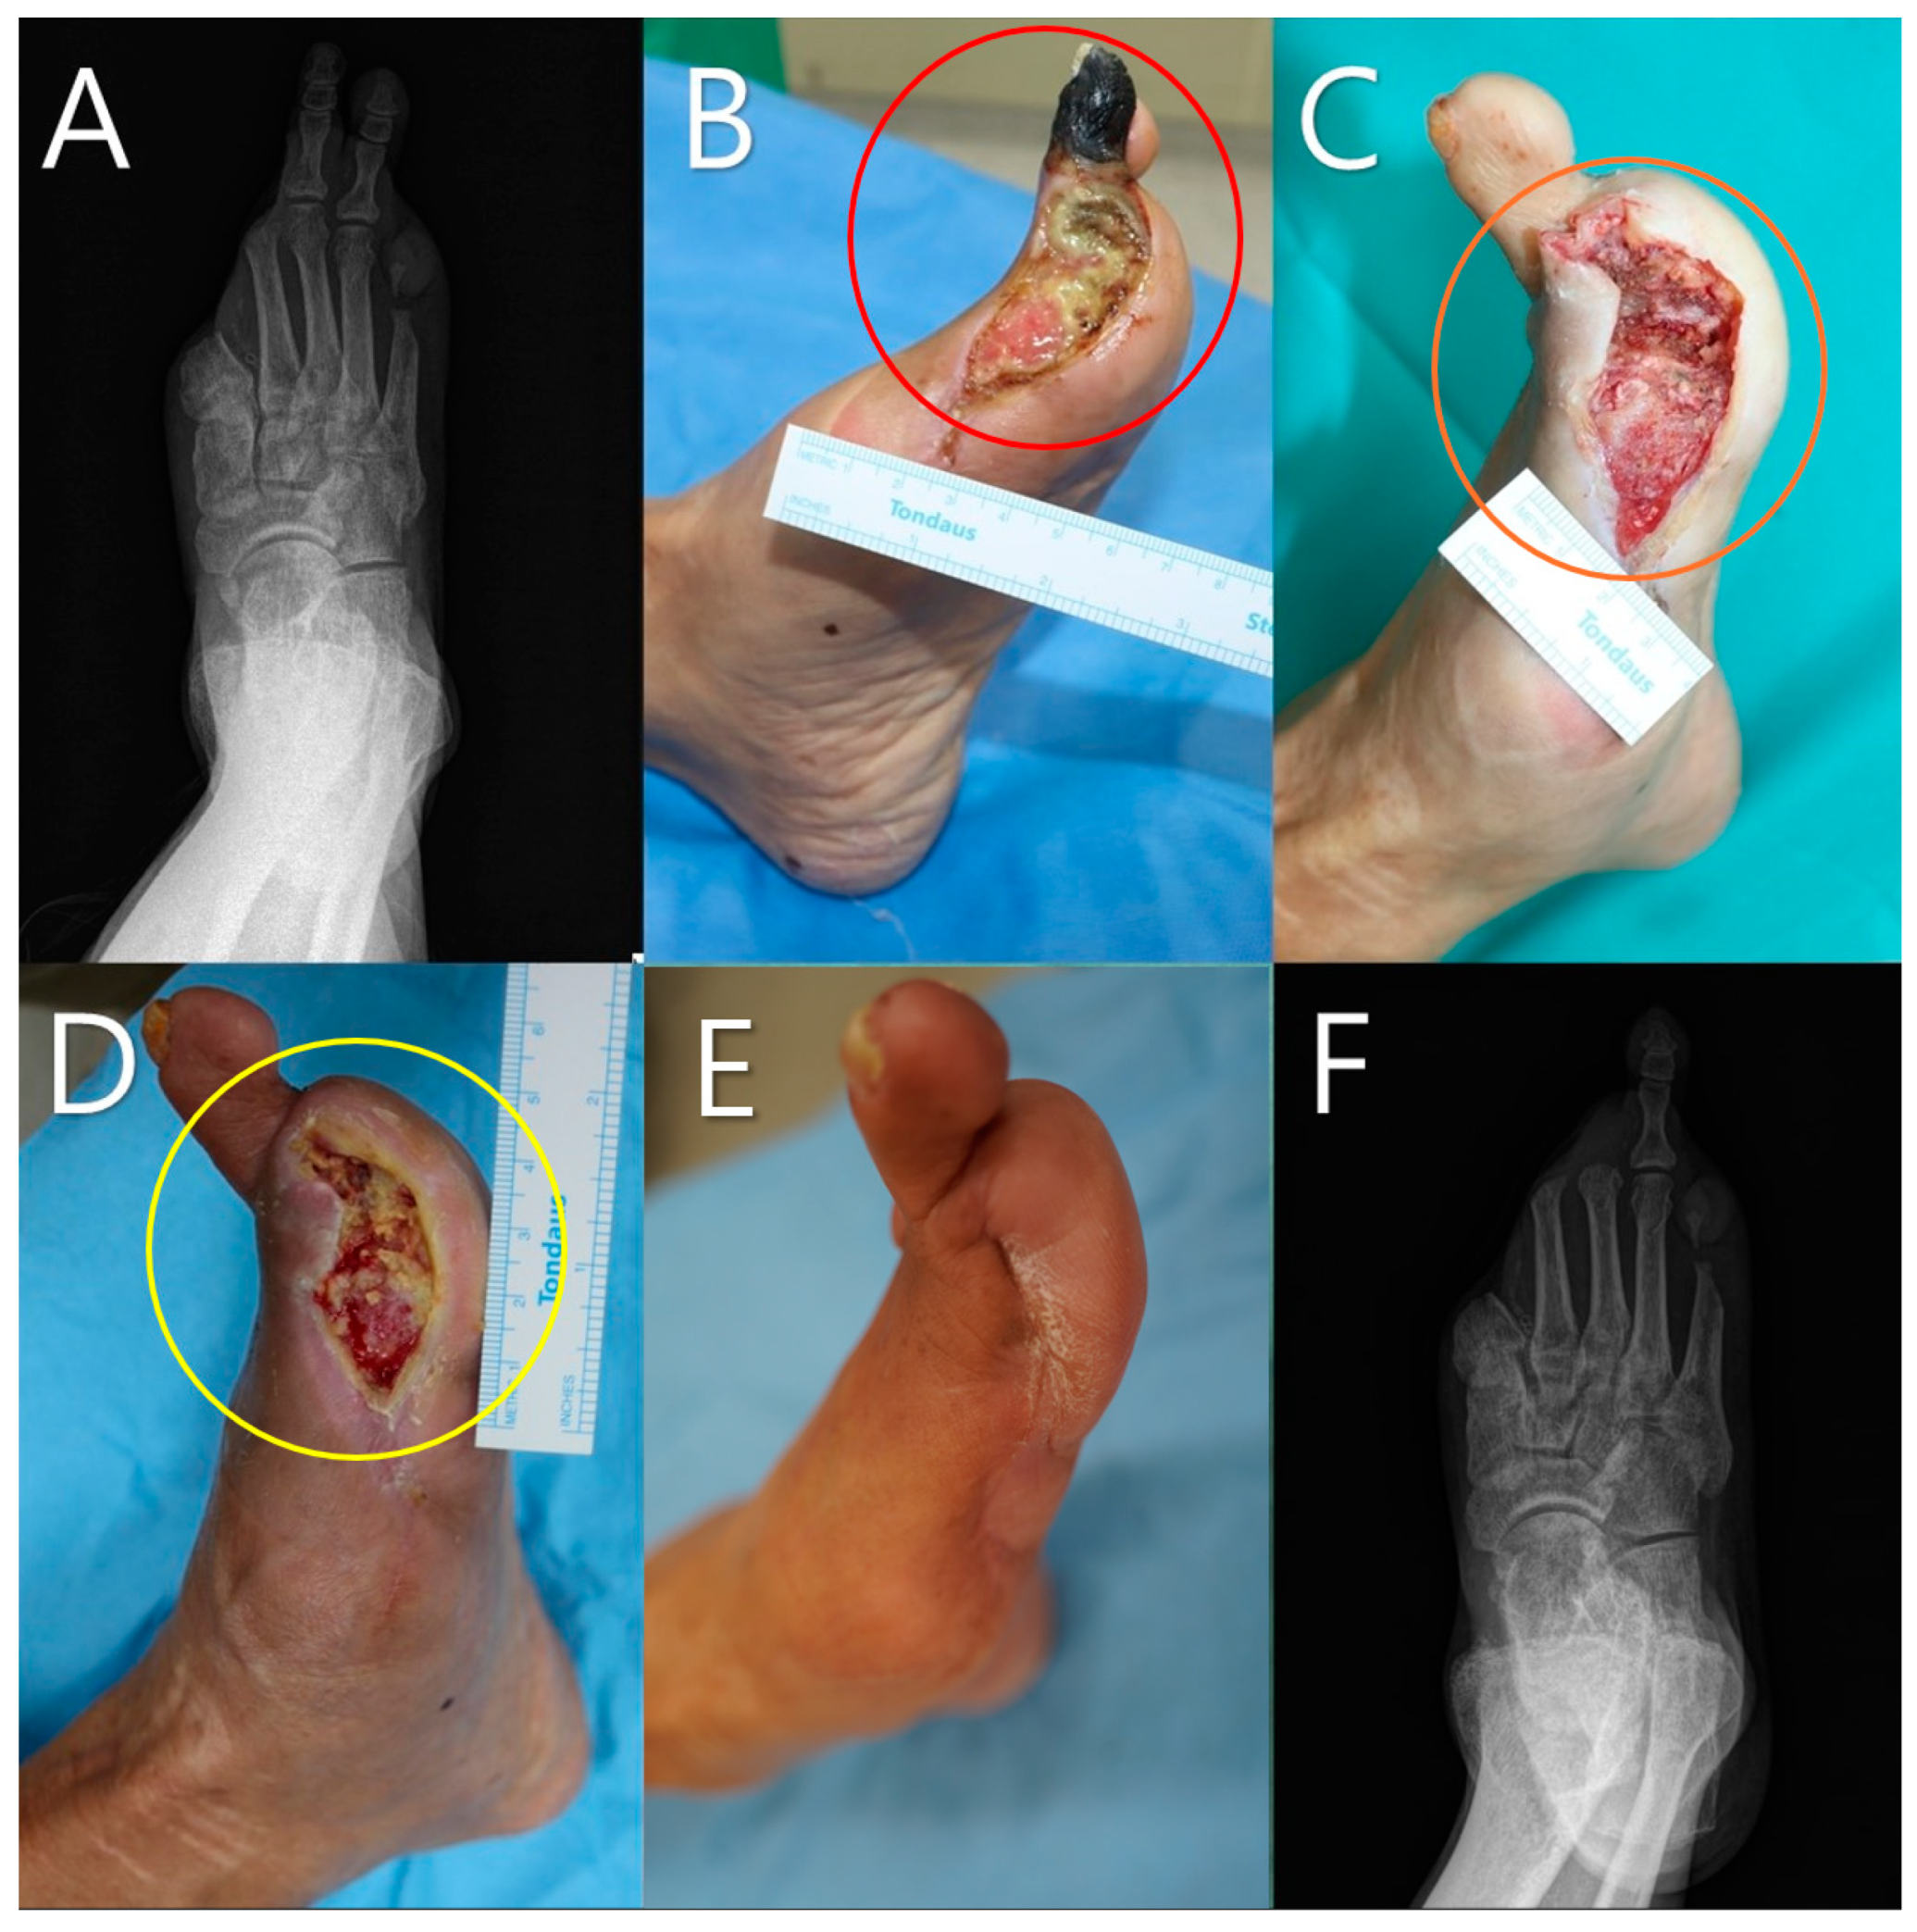

A 65-year-old male patient with a history of diabetes and peripheral arterial disease presented with severe foot ulcer (Figure 7). The initial X-ray revealed extensive bone involvement (Figure 7A). Prior to debridement, clinical examination revealed necrotic tissue and exposed bone (red circle, Figure 7B). Following debridement, the wound bed was prepared for mADM application (orange circle, Figure 7C). A total of five mADM applications were performed over the 3-week treatment period as part of a serial application approach, resulting in significant granulation tissue formation and healing progress being observed (yellow circle, Figure 7D). At the 8-week follow-up, substantial re-epithelialization occurred (Figure 7E). The final X-ray confirmed successful wound closure despite the presence of a bone defect (Figure 7F).

Figure 7.

A 65-year-old male patient with a history of diabetes and peripheral arterial disease. (A) Initial X-ray showing the extent of bone involvement. (B) Clinical photograph prior to debridement, highlighting the necrotic tissue and bone exposure (red circle). (C) Post-debridement image showing the wound bed before micronized acellular dermal matrices (mADMs) application (orange circle). (D) Wound after 3 weeks following a total of five mADM applications, demonstrating significant granulation and healing progress (yellow circle). (E) Wound at the 8-week follow-up, showing re-epithelialization. (F) Final X-ray showing successful healing despite the presence of a bone defect, indicating effective re-epithelialization and wound closure.